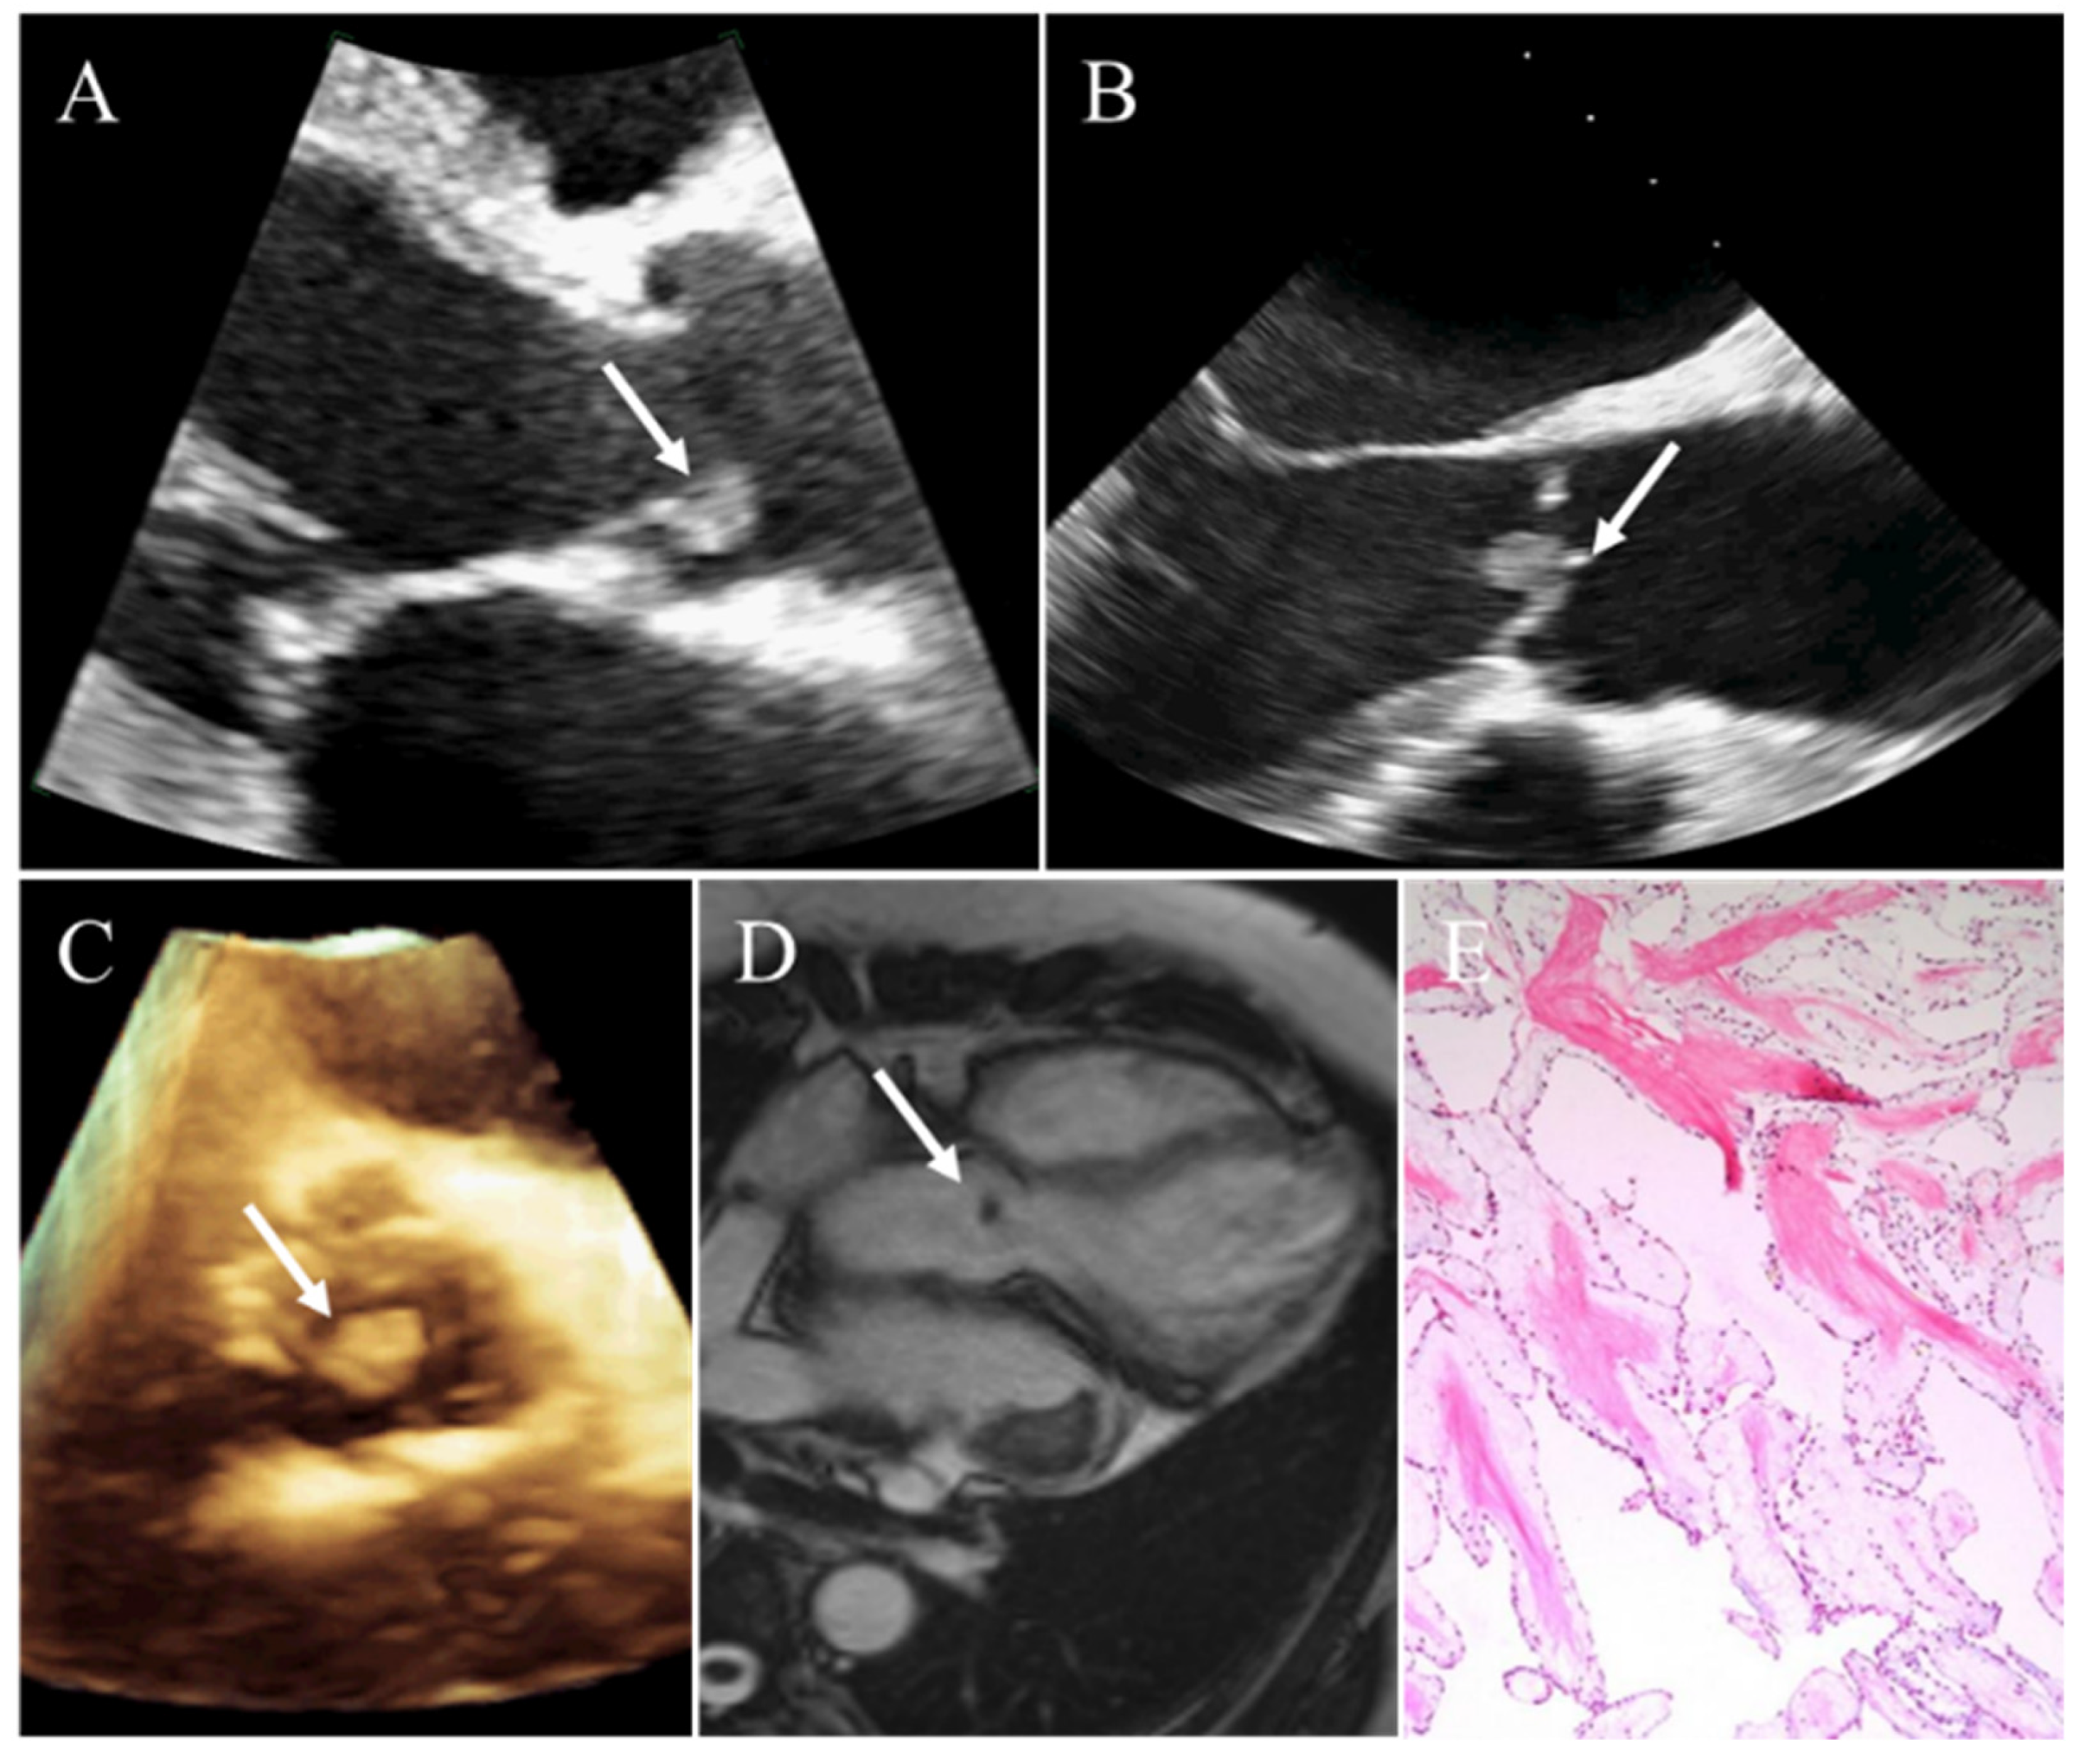

4.1. Myxoma

| Myxoma | Middle age (30–60 y); younger if associated with Carney complex | Females | Left atrium; attached to the fossa ovalis | Heterogeneous; narrow pedicle; regular mobile throughout the cardiac cycle | Heterogeneous; low-attenuation; calcification seen in 10–20% of patients | Smooth, well-defined, lobular or oval; heterogeneous; isointense on T1WI; hyperintense on T2WI; heterogeneous enhancement |

- Wang, H.; Li, Q.; Xue, M.; Zhao, P.; Cui, J. Cardiac myxoma: A rare case series of 3 patients and a literature review. J. Ultrasound Med. 2017, 36, 2361–2366. [Google Scholar] [CrossRef] [PubMed]

- Colin, G.C.; Gerber, B.L.; Amzulescu, M.; Bogaert, J. Cardiac myxoma: A contemporary multimodality imaging review. Int. J. Cardiovasc. Imaging 2018, 34, 1789–1808. [Google Scholar] [CrossRef]

- Li, X.; Chen, Y.; Liu, J.; Xu, L.; Li, Y.; Liu, D.; Sun, Z.; Wen, Z. Cardiac magnetic resonance imaging of primary cardiac tumors. Quant. Imaging Med. Surg. 2020, 10, 294–313. [Google Scholar] [CrossRef]

- Abbas, A.; Garfath-Cox, K.A.; Brown, I.W.; Shambrook, J.S.; Peebles, C.R.; Harden, S.P. Cardiac mr assessment of cardiac myxomas. Br. J. Radiol. 2015, 88, 20140599. [Google Scholar] [CrossRef]